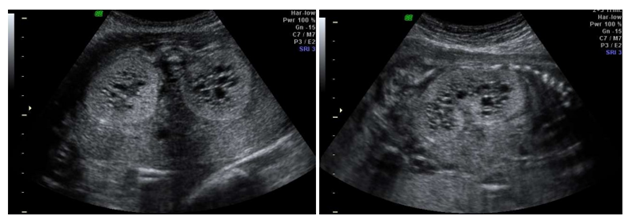

Gestante, 28 anos, primigesta, com 23 semanas de idade gestacional, vem para realização de rotina de

ultrassonografia morfológica fetal, apresentando o seguinte achado associado a anidramnia.

Sobre tal patologia em questão, é CORRETO afirmar:

Sobre tal patologia em questão, é CORRETO afirmar: